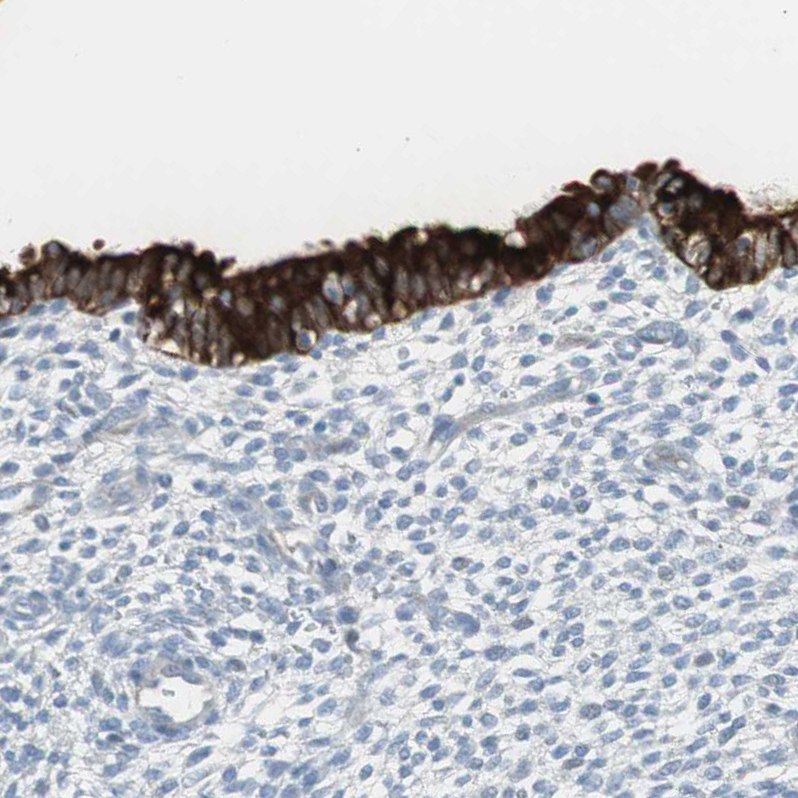

Immunohistochemistry analysis in human stomach and skeletal muscle tissues using HPA007912 antibody. Corresponding AGR2 RNA-seq data are presented for the same tissues.